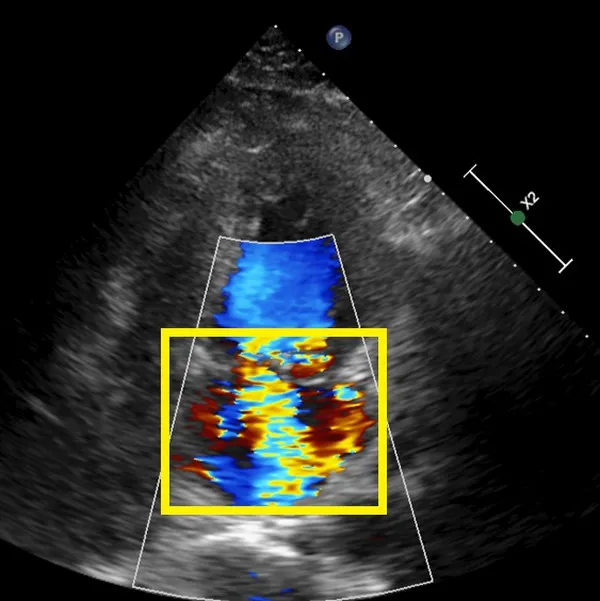

台北慈濟心血管醫學中心主任張燕表示,若只是單純二尖瓣逆流,有機會靠微創手術治療,但蔡先生的二尖瓣不但逆流,還有一個1公分左右的大破損,周圍更出現許多細菌感染增生的贅生物,使得抗生素藥物治療效果有限。